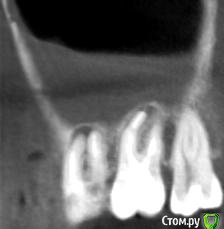

Helen22 Опубликовано 12 декабря, 2015 Автор Поделиться Опубликовано 12 декабря, 2015 Спасибо за оперативные ответы) промучилась с этим КТ(оно действительно для ЛОРа), но не смогла ничего в нем сделать.Сделала сегодня КТ 16, 17, 18 вот принт- скрины, правда не знаю насколько они будут информативными.... Ссылка на комментарий